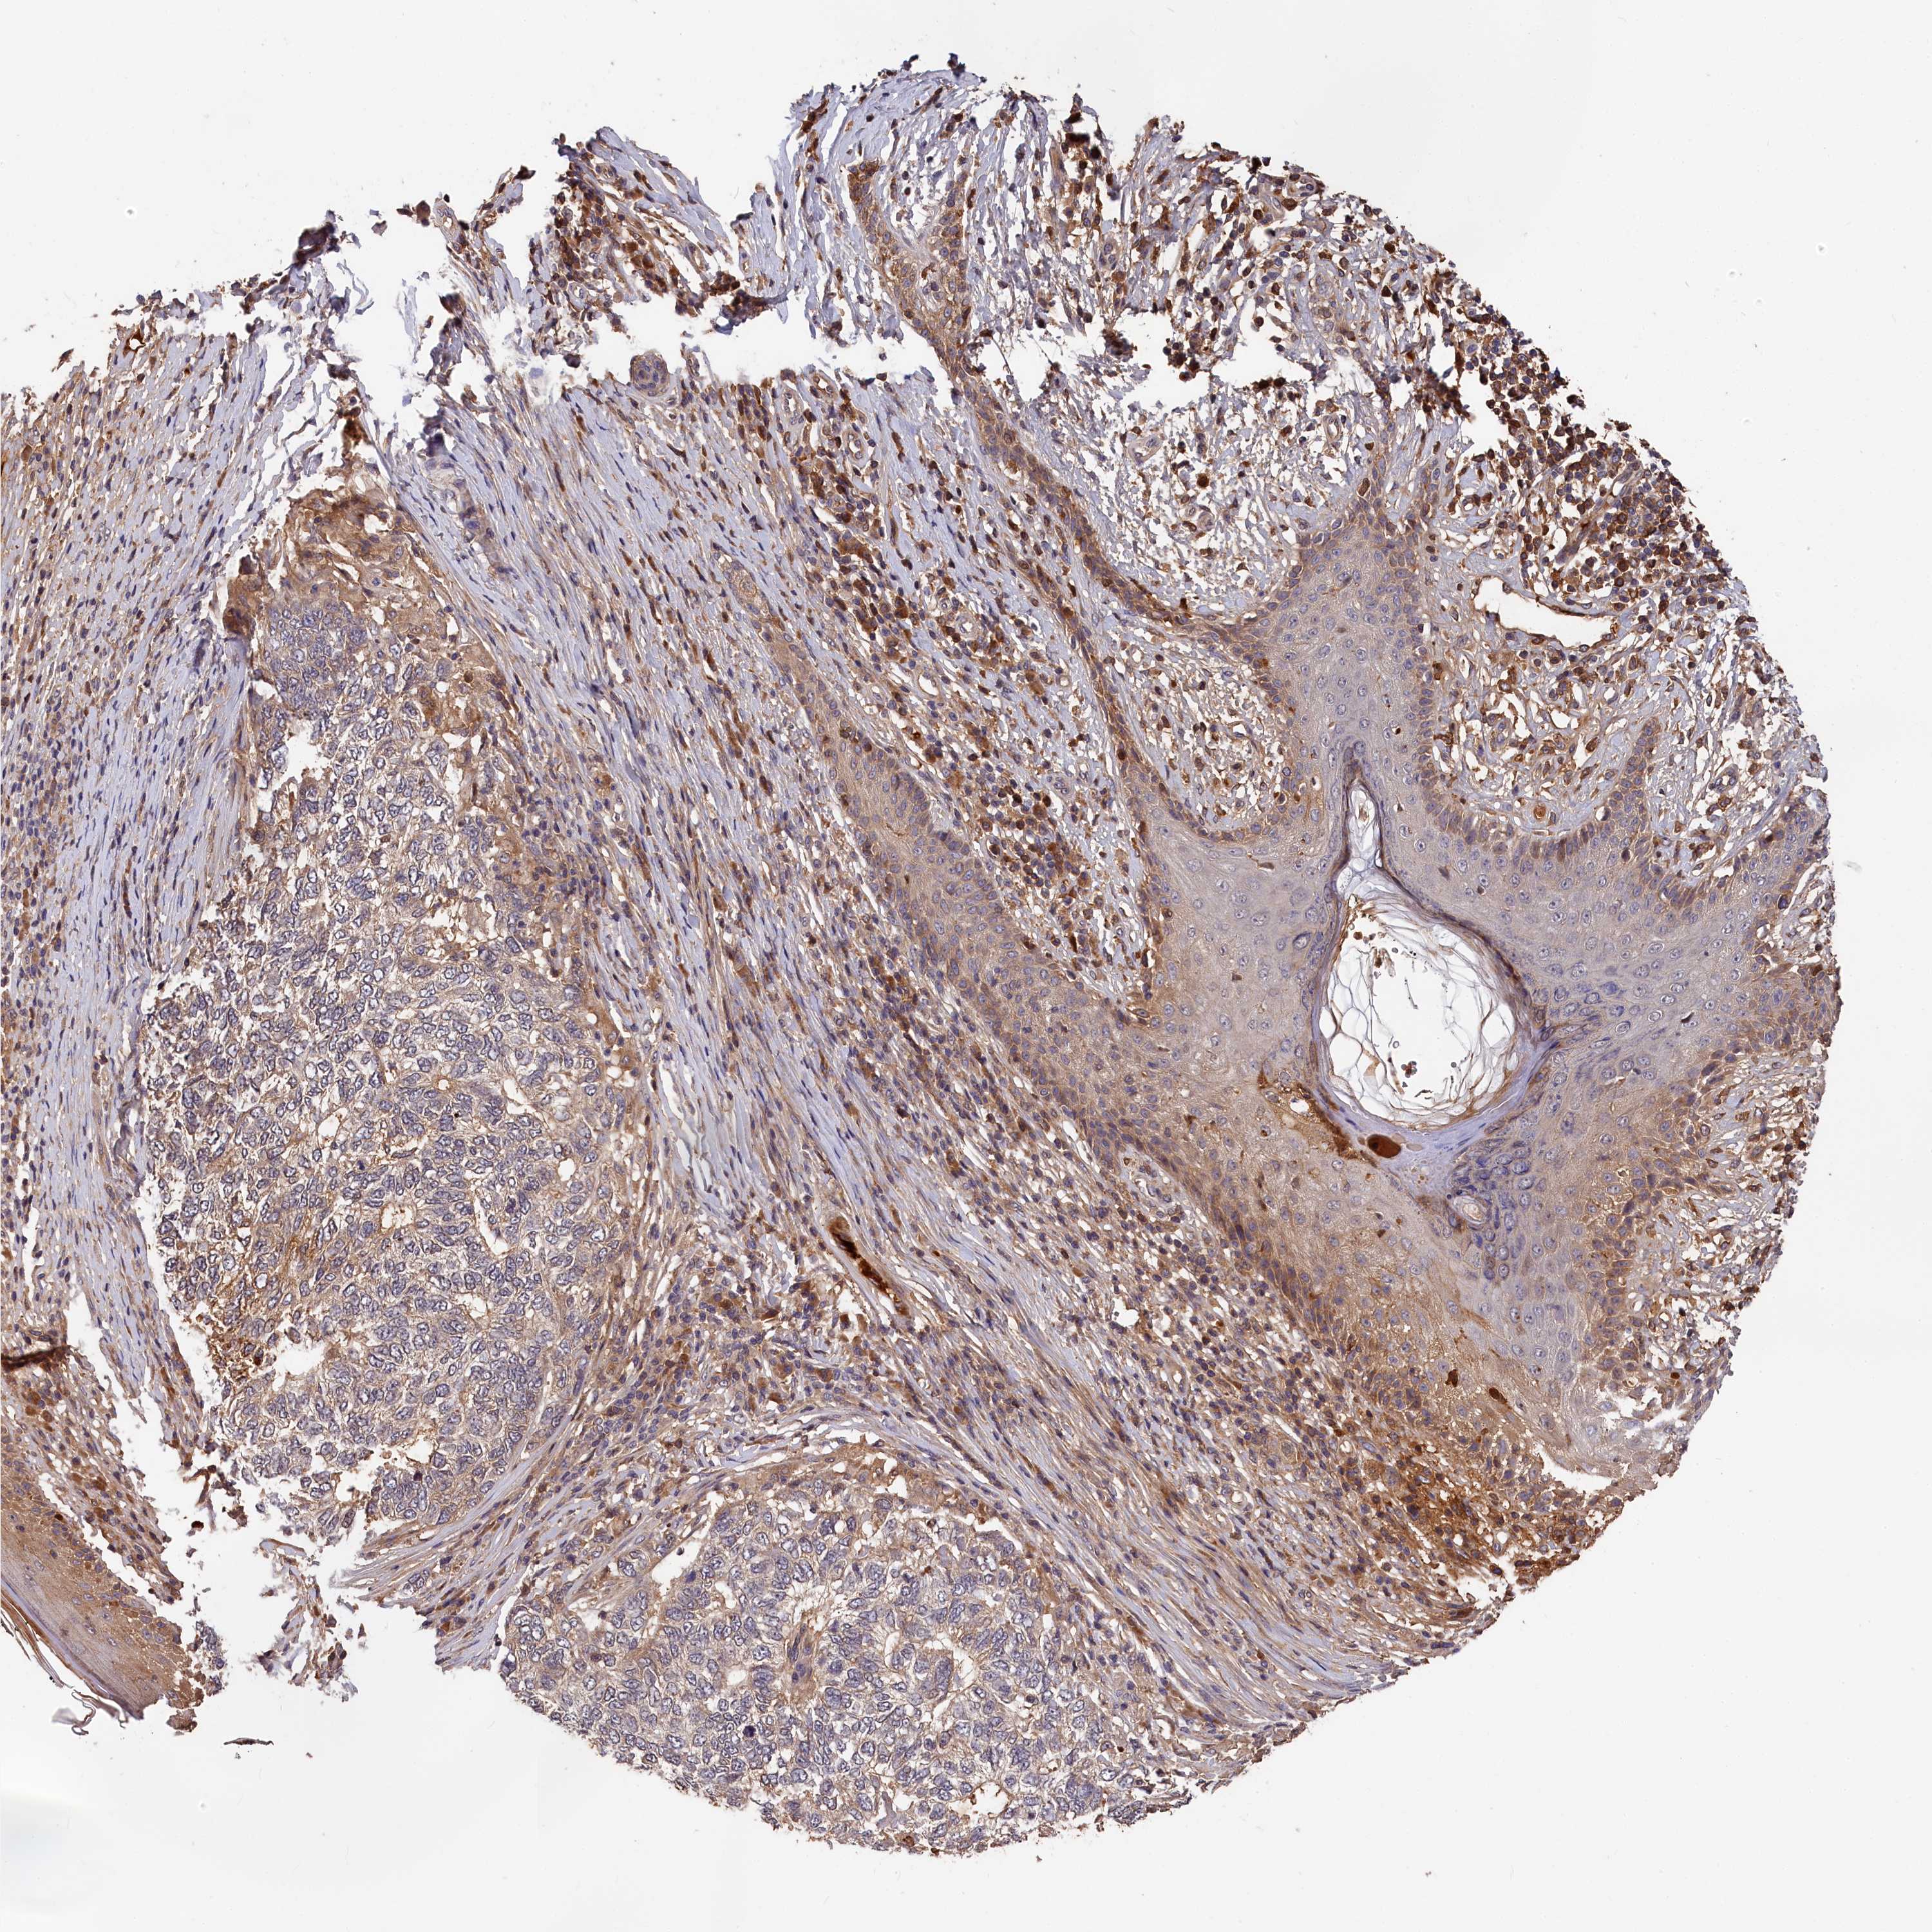

SKIN CANCER - Protein expressioni

A mouse-over function shows sample information and annotation data. Click on an image to view it in a full screen mode. Samples can be filtered based on level of antibody staining by selecting one or several of the following categories: high, medium, low and not detected. The assay and annotation is described here.

Antibody stainingi

Antibody staining in the annotated cell types in the current human tissue is reported as not detected, low, medium, or high, based on conventional immunohistochemistry profiling in selected tissues. This score is based on the combination of the staining intensity and fraction of stained cells.

Each image is clickable and will lead to virtual microscopy that enables deeper exploration of all samples and also displays staining intensity scores, fraction scores and subcellular localization as well as patient and tissue information for each sample.

Antibody HPA041639

Antibody HPA042049

Squamous cell carcinoma, NOS